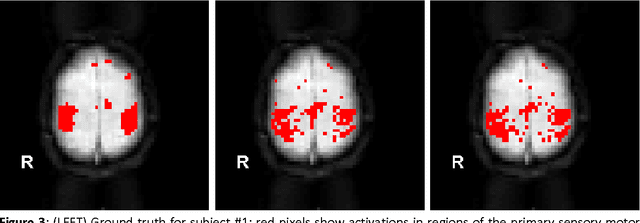

Abstract:We present a computational framework for analysis and visualization of non-linear functional connectivity in the human brain from resting state functional MRI (fMRI) data for purposes of recovering the underlying network community structure and exploring causality between network components. Our proposed methodology of non-linear mutual connectivity analysis (MCA) involves two computational steps. First, the pair-wise cross-prediction performance between resting state fMRI pixel time series within the brain is evaluated. The underlying network structure is subsequently recovered from the affinity matrix constructed through MCA using non-metric network partitioning/clustering with the so-called Louvain method. We demonstrate our methodology in the task of identifying regions of the motor cortex associated with hand movement on resting state fMRI data acquired from eight slice locations in four subjects. For comparison, we also localized regions of the motor cortex through a task-based fMRI sequence involving a finger-tapping stimulus paradigm. Finally, we integrate convergent cross mapping (CCM) into the first step of MCA for investigating causality between regions of the motor cortex. Results regarding causation between regions of the motor cortex revealed a significant directional variability and were not readily interpretable in a consistent manner across all subjects. However, our results on whole-slice fMRI analysis demonstrate that MCA-based model-free recovery of regions associated with the primary motor cortex and supplementary motor area are in close agreement with localization of similar regions achieved with a task-based fMRI acquisition. Thus, we conclude that our computational framework MCA can extract and visualize valuable information concerning the underlying network structure and causation between different regions of the brain in resting state fMRI.